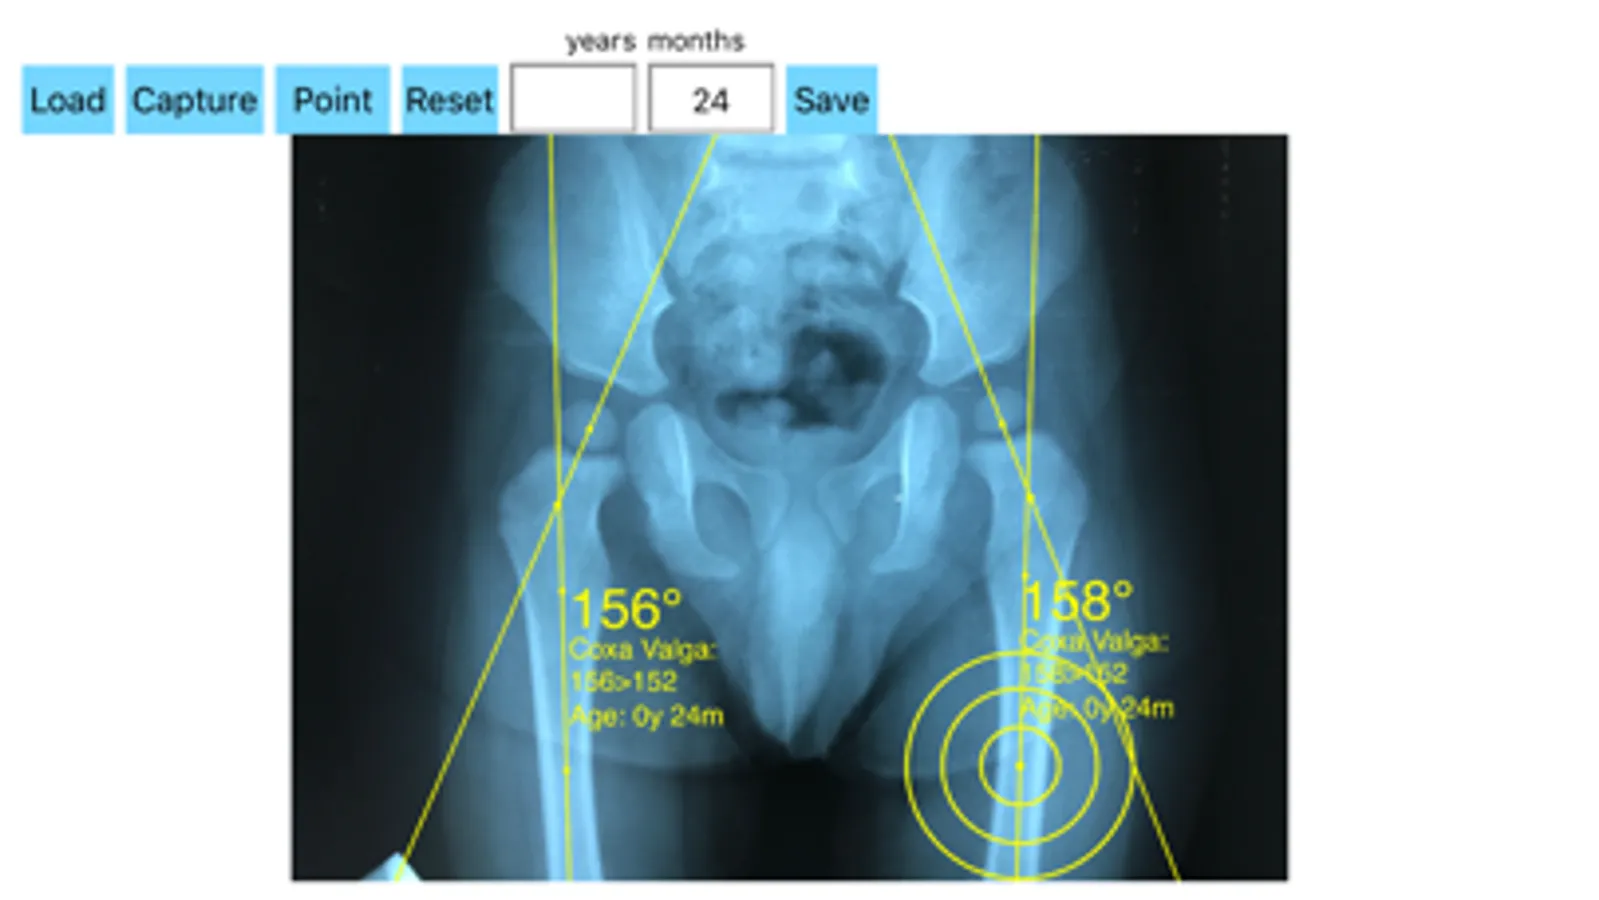

-Offers a very convenient way to determine the most accurate possibly lines in order to measure the angle. By the aid of a circular template, four points of interest are marked. The automatically formed lines drawn between points give an angle which is measured automatically by the App. The visualized results are in degrees.

By inputing the age of the patient in the App, the measured angle is compared with values from normal reference database (see reference) according the patient age. In case the measured angle is increased or decreased, the hip is valgus or varus respectively.